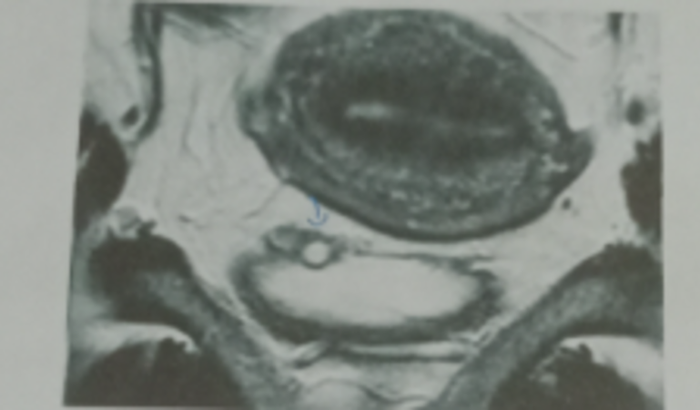

Eu sou a Márcia e venho por meio dessa vaquinha contar um pouco da minha história, depois q nasceu minha filha fui varia vezes ao médico falar q sentia dores muito fortes na região pelve mas ele só passava trans vaginal e nada constava ao passar dos anos resolver ir a outro médico pois a mesma me pediu uma ressonância pelve e foi constatado hendromentiose profunda com adenomiose e um cisto na região da bexiga e por isso estou aqui pedindo ajuda pois e muito urgente a cirurgia tá colando no meu estômago já por favor me ajude Deus abençoe a todos amém